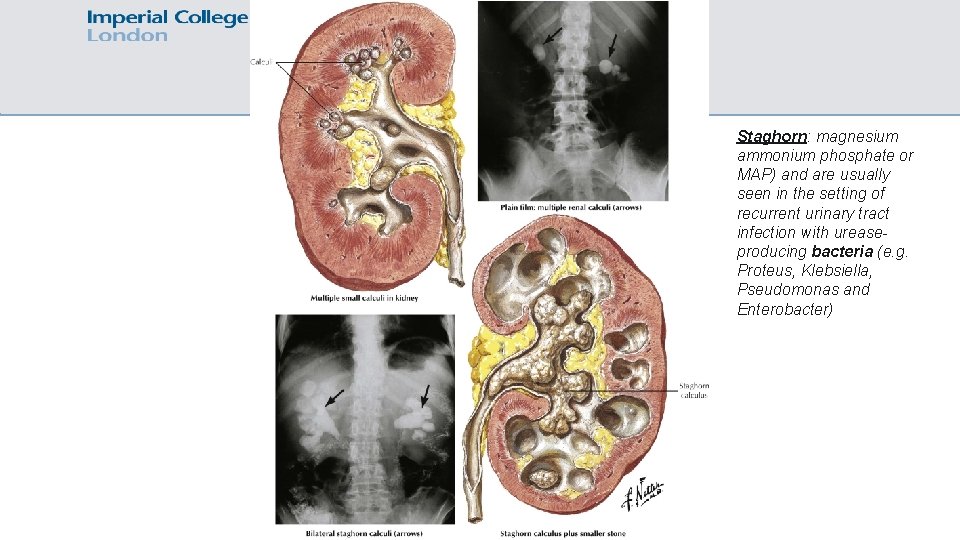

Staghorn: magnesium ammonium phosphate or MAP) and are usually seen in the setting of recurrent urinary tract infection with ureaseproducing bacteria (e. g. Proteus, Klebsiella, Pseudomonas and Enterobacter)